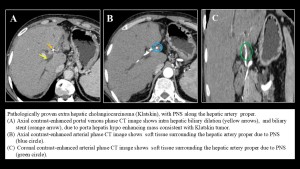

Cholangiocarcinoma

Cholangiocarcinoma, whether extrahepatic or intrahepatic, is an aggressive malignancy with poor prognosis. Recurrence is often driven by nodal metastases and extensive perineural spread.

- In extrahepatic tumors, PNS typically occurs through the posterior hepatic plexus, a large tributary of the celiac plexus along the common hepatic artery as well as the posterior inferior pancreaticoduodenal artery and the superior mesenteric artery.

- In intrahepatic tumors, right-lobe lesions spread along the common hepatic artery, while left-lobe lesions follow the left gastric artery. Both pathways ultimately lead to involvement of celiac ganglia.